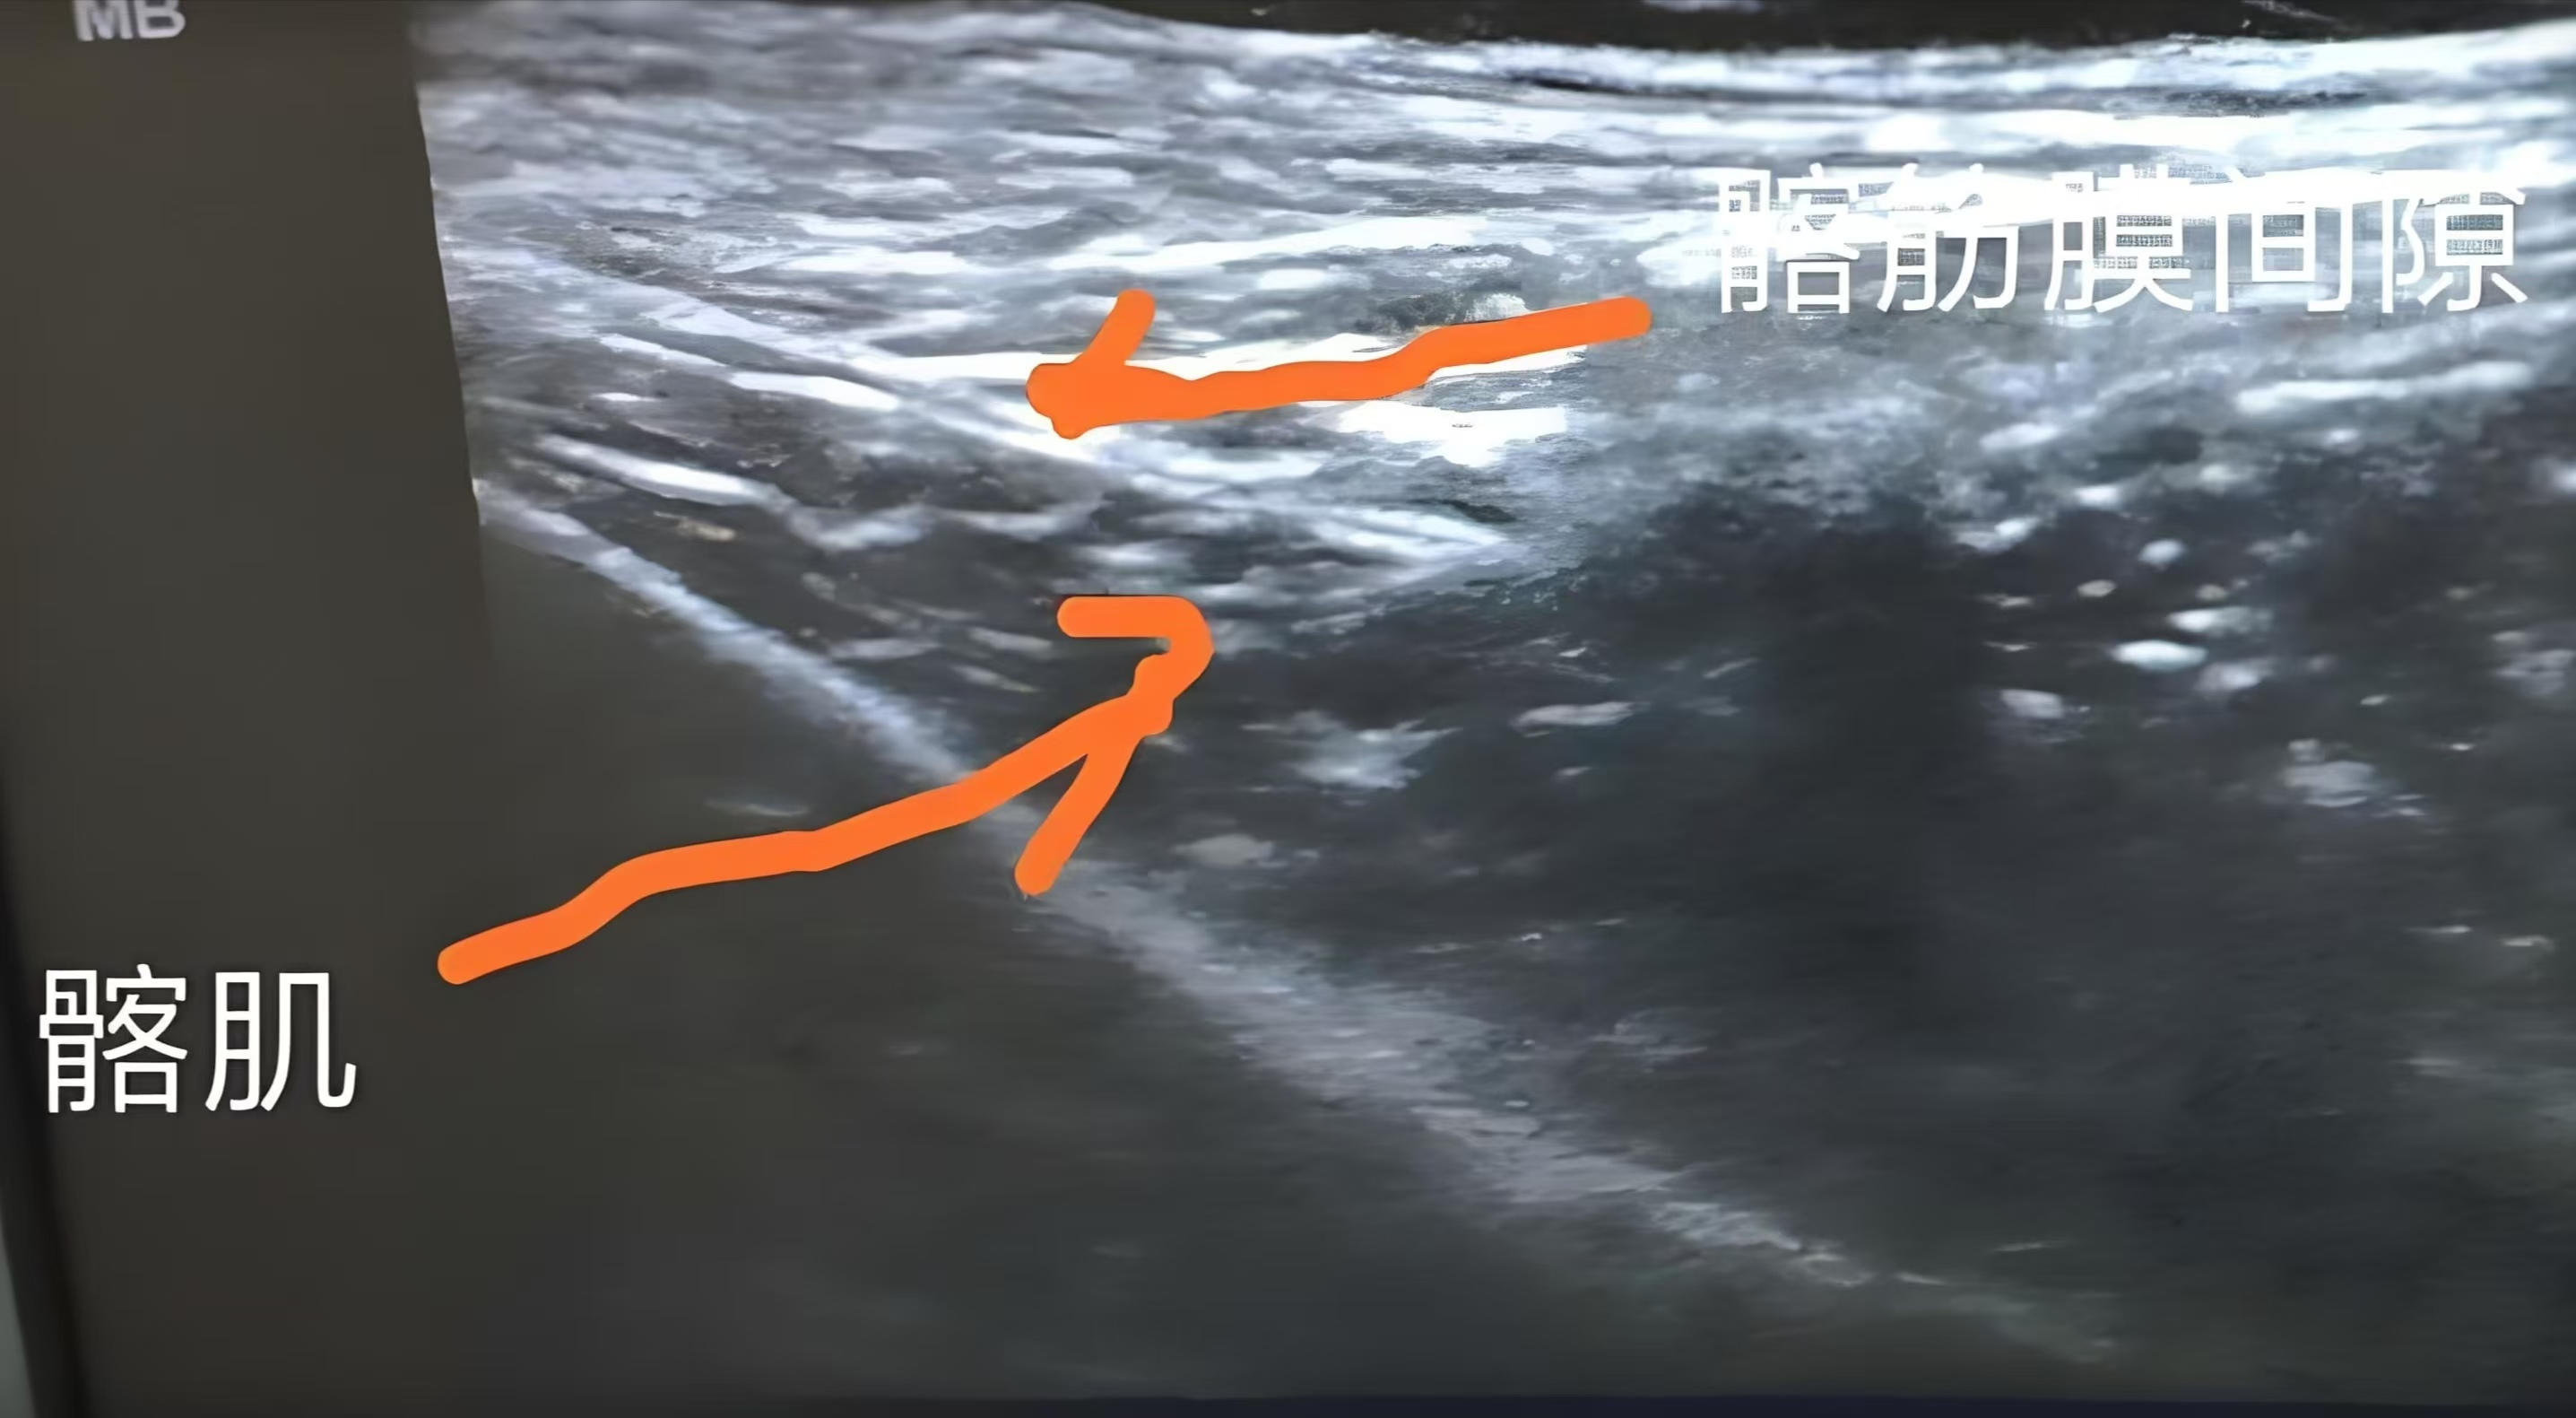

超声引导下的髂筋膜阻滞的方法和定位: 在超声引导下,麻醉医生使用超声探头在腹股沟韧带上方识别定位髂骨、髂肌及缝匠肌、腹外斜肌,髂肌的上方即为髂筋膜,穿刺针刺入髂筋膜注入局麻药0.25%罗哌卡因30-40ml,可见麻醉药沿着髂筋膜扩散,髂肌被推向下方。

超声引导下的髂筋膜阻滞在成功率和定位方面具有显著优势。通过超声影像,麻醉医生能够清晰地看到髂筋膜的位置和周围组织结构,从而准确地完成神经阻滞操作。操作简单,效果安全可靠。